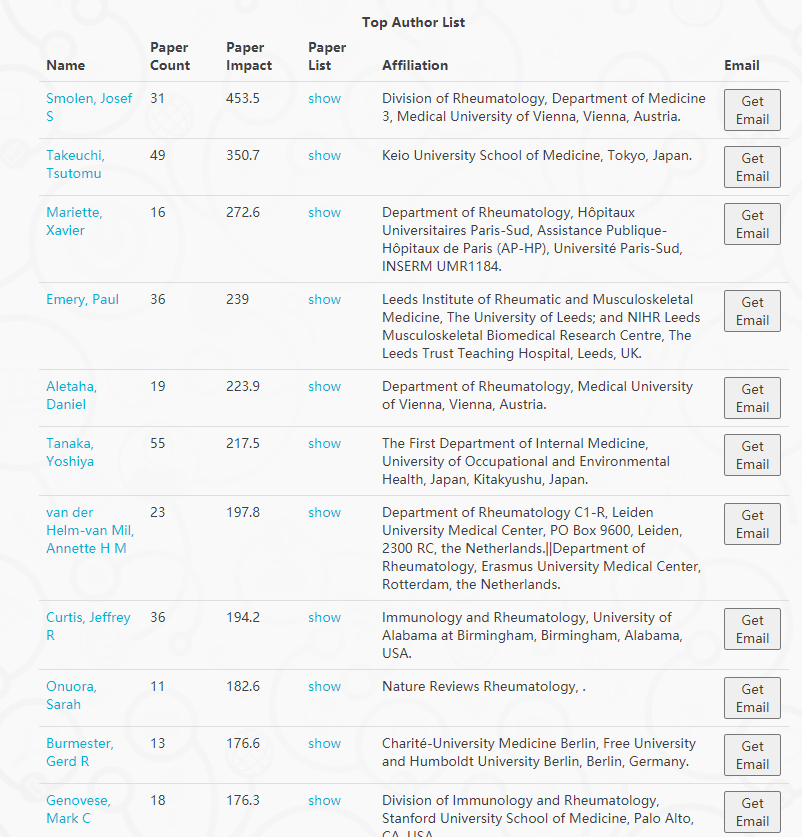

类风湿关节炎临床科研谁家强